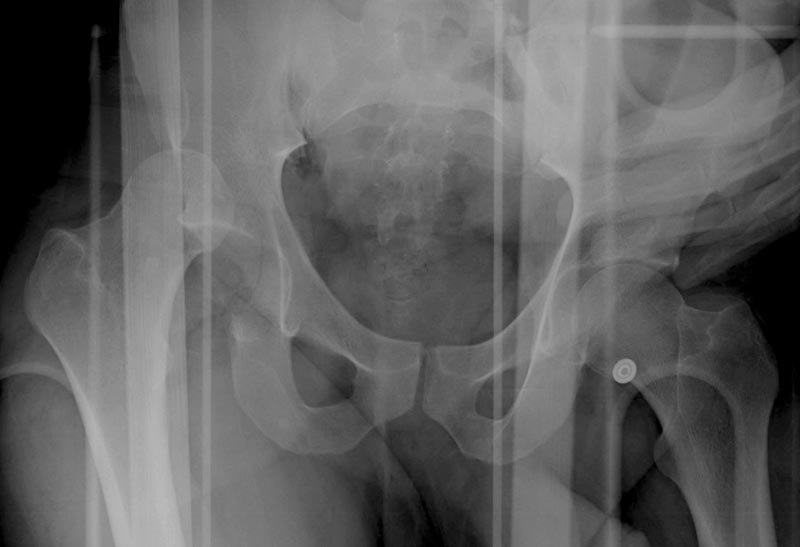

5:24 Рентгенограмма таза, вызывают врача ортопеда (снимок N1), его диагноз: закрытый переломо-вывих правого тазабедренного сустава, получает добро на закрытую репозицию в приемном отделении

5:38 Дважды неудачная попытка закрытой репозиции в приемном отделении

N 2

6:20 ответстенный врач принимает решение о репозиции в условиях операционной, предупреждаются родственники и больной, что при неудачной закрытой репозиции, о возможности открытой репозиции и фиксации задней стенки вертлужной впадины.